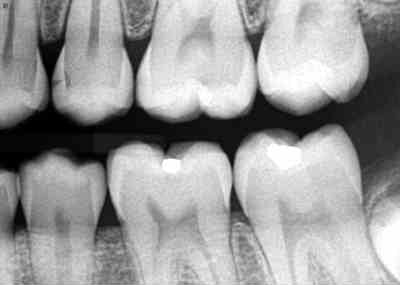

“A picture is worth a thousand words” and there is no exception to this for your dentist. Dental radiographs (images created with the use of ionizing radiation) are dental pictures that serve as an important tool to aid the human eye of the dentist in the detection and diagnosis of diseases, lesions, and health of the teeth and bone. Radiographs serve as an extra pair of eyes for seeing things that can’t be seen by just looking in the mouth.

Once the need for dental radiographs has been decided, trained dental professionals are expected to use radiation safely. Dental offices use the ALARA (as low as reasonably achievable) principle that states all exposures to radiation must be kept to a minimum. This is done in several ways such as the use of digital sensors which can reduce the dose from 50 to 90% compared to traditional film, a lead apron with a thyroid collar, sensor holders to stabilize the sensor in the mouth, appropriate exposure time and settings, and proper technique to ensure the quality of the image.

The amount of ionizing radiation used in dentistry is considered a low dose because it is focused just on the mouth. For example, a full mouth series of digital radiographs is equal to approximately 20 days of exposure to background radiation. The risk of getting cancer from dental x-rays would be comparable to a 1 in 1 million risk of death due to an accident while traveling 1000 miles in airplane or 300 miles in an automobile. One must also keep in mind that the human body is composed of trillions of cells. Cells have ways of repairing damage that may be caused by radiation.